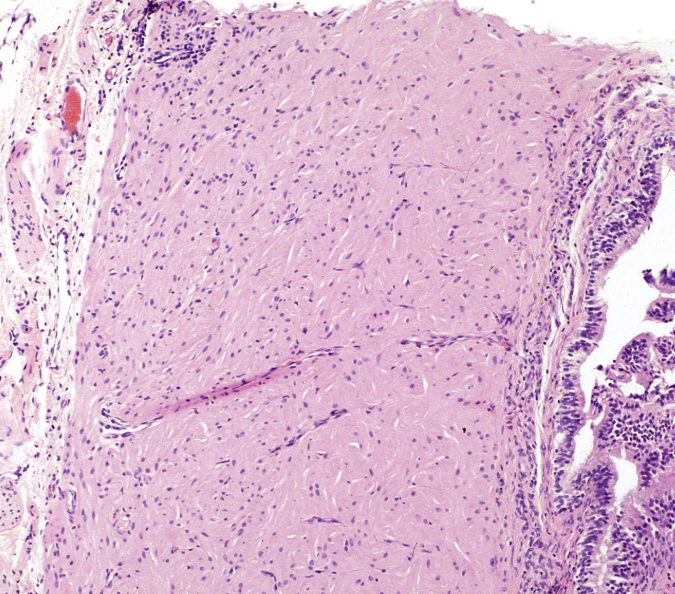

De la siguiente imagen microscópica podemos afirmar lo siguiente: